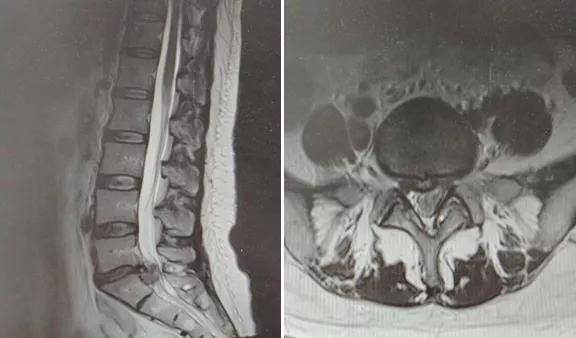

MRI检查

MRI , 即核磁共振检查 , 有良好的软组织分辨率 , 对骨关节内结构、骨髓及软组织病变的显示优于DR和CT , 但难以分辨骨软组织内较细小的钙化或骨化 , 骨皮质的显示也不如DR和CT 。 MRI扫描可以清晰观察病变椎间盘突出的部位、程度、形态及其与周围组织的关系 , 对神经根的压迫程度及是否出现椎间盘脱出、游离 , 对手术方案制定有重要意义 。

文章图片